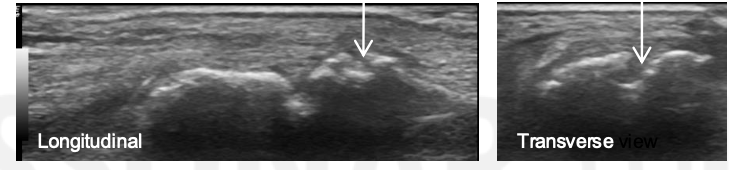

What is the arrow pointing to?

Synovial Distension